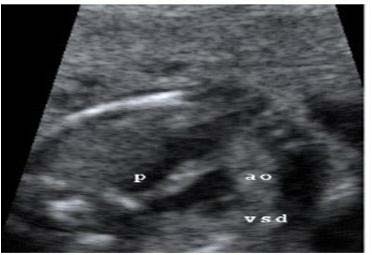

A los 23 días de vida, el recién nacido comenzó con dificultades para tragar. Con sus antecedentes, se realizó un esofagograma con contraste baritado, objetivándose una indentación lateral izquierda en esófago medio, sugerente de anomalía vascular. (Figura2).

Figura 2. Esofagograma con contraste baritado